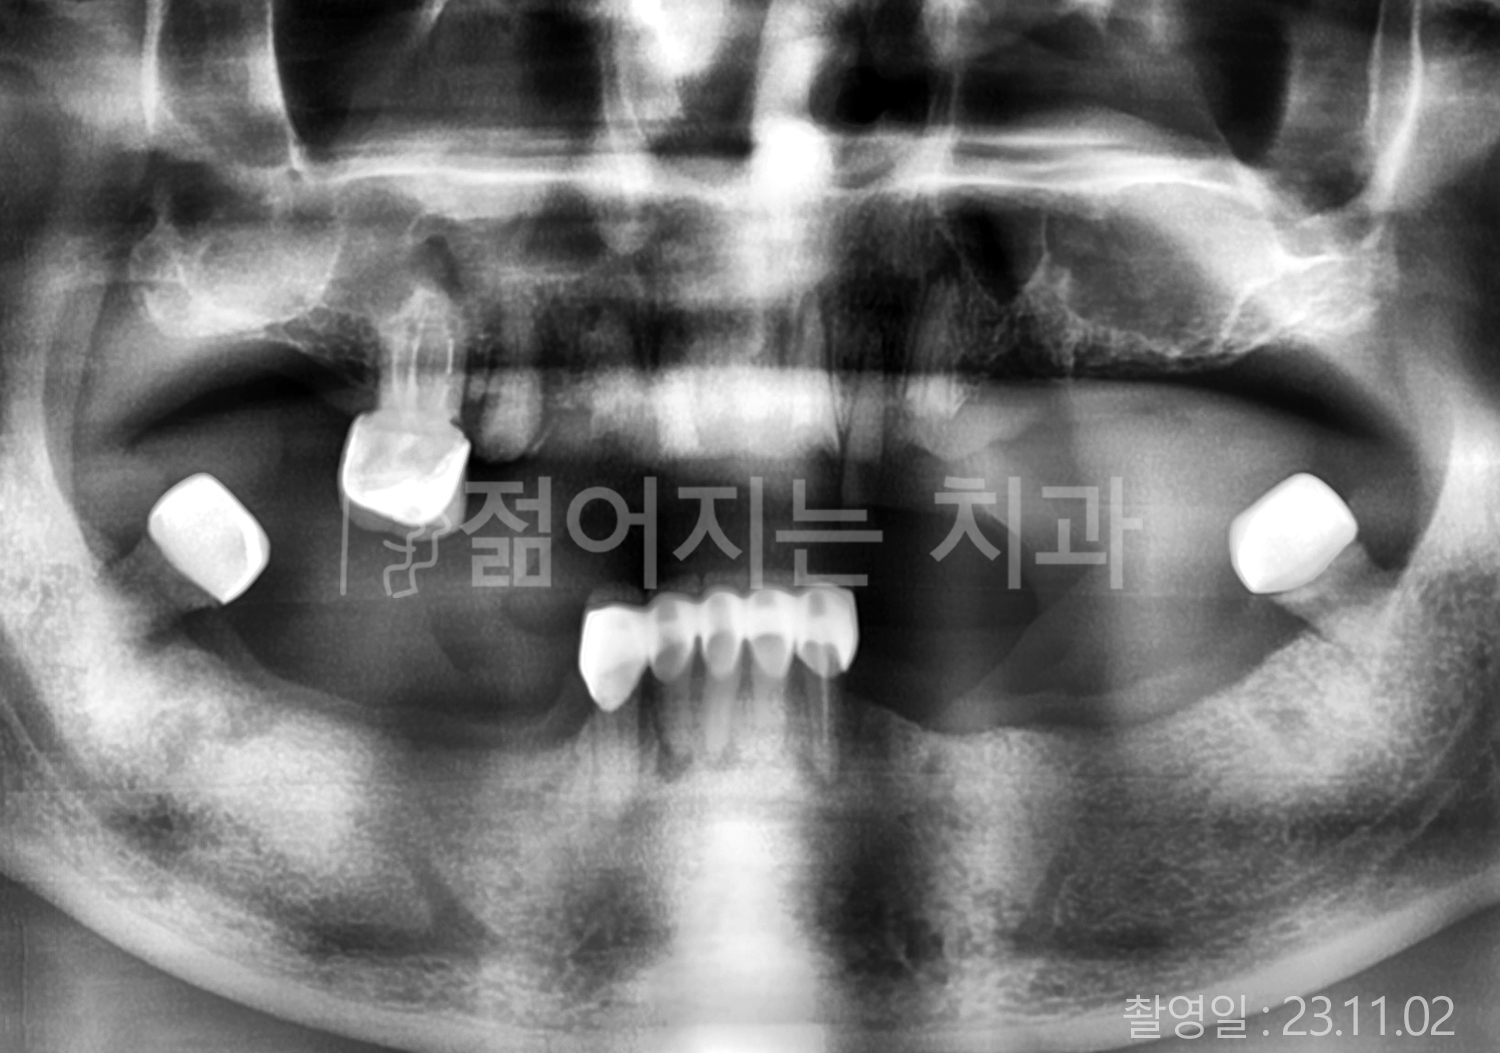

• 60대 전체치아 10개 이상 임플란트